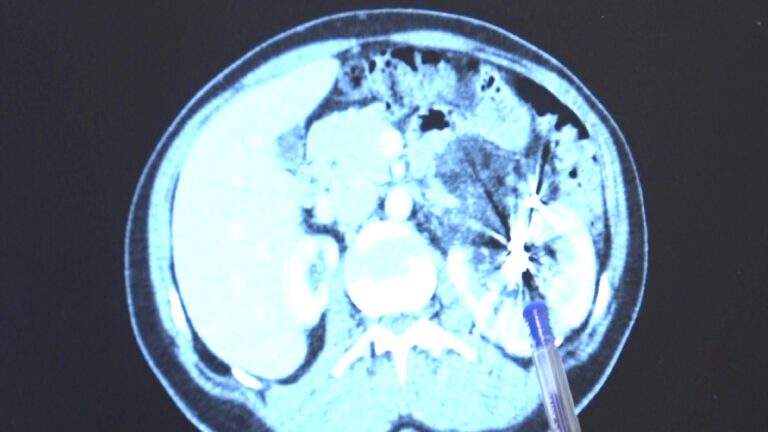

Yıllar sonra çekilen MR da tek böbrekte kitle bulunmuş ve bunun üzerine iyi huylu kitleye iki defa embolizasyon sürecinin yapıldığı açıklandı. Kitlenin büyümeye devam etmesiyle gittiği tabiplerden böbreğinin alınması gerektiğini duyan Avcı’nın, Bursa’da 2 saatlik kapalı bir operasyonla sağlığına kavuşturulduğu bildirildi.

Hastanın, sağlam böbreğinde büyüyen iyi huylu ‘anjiomyolipomu’ ismi verilen 12 santimetre boyutunda bir kitlenin tedavisi tamamlandığı bildirildi. Bayanlarda 4 santimetreden büyük anjiomyolipomuların zaten kanayarak hayatı tehlikeye atması nedeniyle bu kitlelerin an kısa vakitte alınması büyük ehemmiyet taşır.